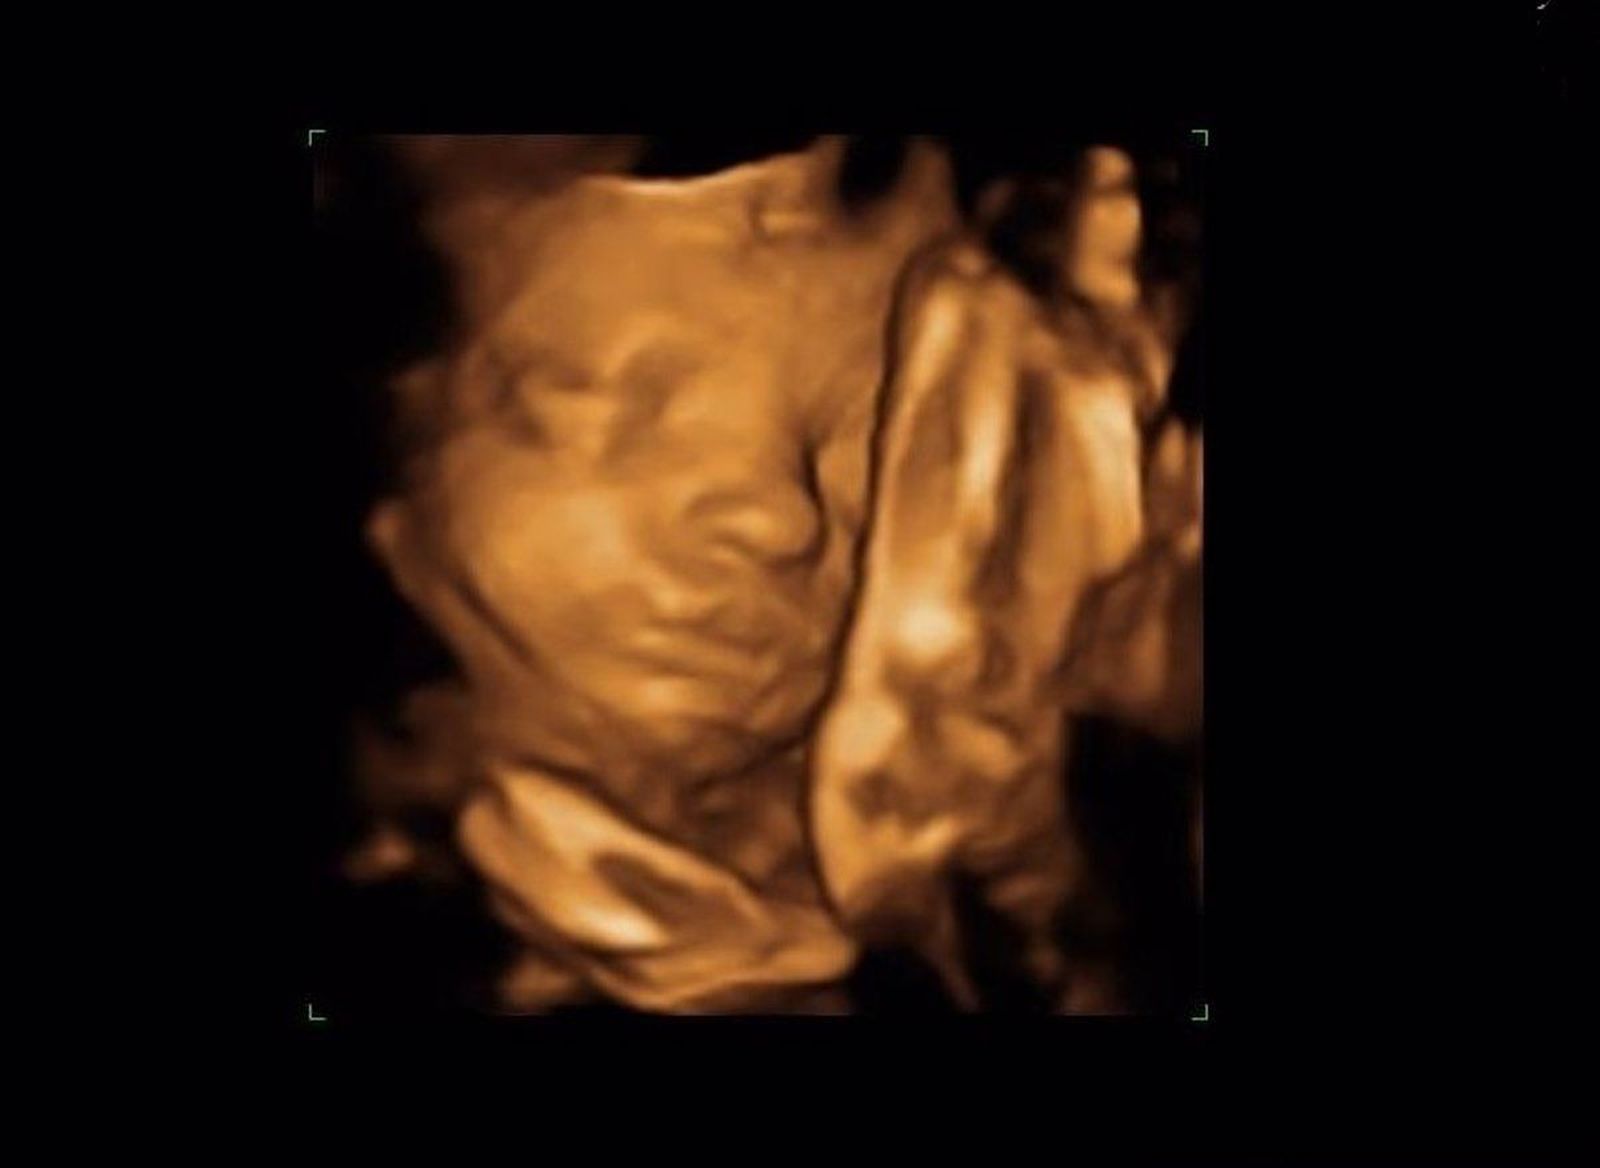

Ecografía. Foto Infosalus